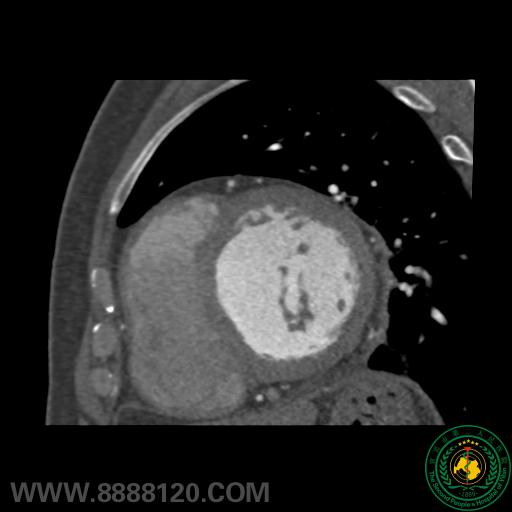

我院开展炫速双源CT对风心病的换瓣或成形术术前、术后评估技术

我院开展炫速双源CT对风心病的换瓣或成形术术前、术后评估技术3891